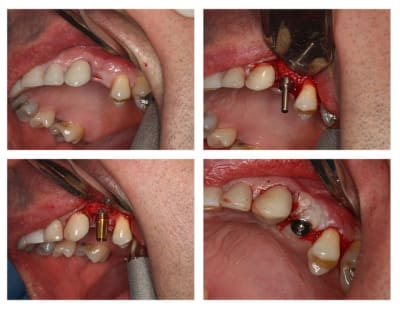

26/01/2010 à 21h40

c'est posé; allez y

le petit trou en palatin de ton moignon, c'est pour quoi?

utilises-tu des piliers de cicatrisation évasés pour préparer à minima ton émergence gingivale?

c'est tout simplement un faux moignon "droit" en titane idi

ils ont tous ce petit trou que j'utilise parfois pour l'enlever, lors des essais

Quel que soit le diamètre de 2,8 à 3,7 le col fait 4mm, cela simplifie la prothèse (peut être trop)

L'axe est effectivement un peu vestibulaire